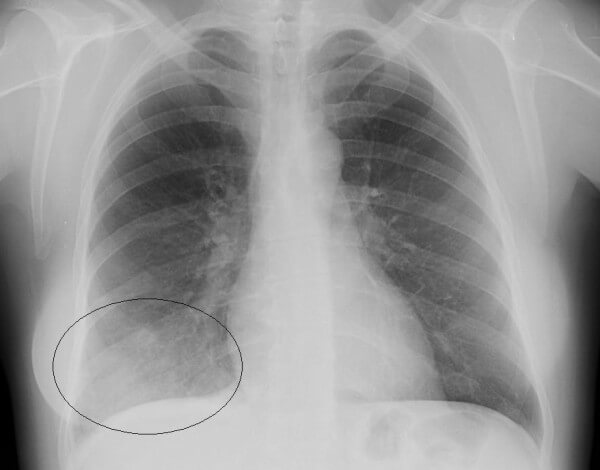

Крупозная пневмония – гиперергическое воспаление, которое проходит следующие стадии: прилив, красное и серое опеченение и период разрешения.

На снимках видно, что воспалительный процесс локализуется лобарно или сублобарно (то есть поражается доля легкого) с вовлечением плевры. Легочный рисунок при этом изменяется, а легочные корни расширяются. Видны застои жидкости в плевральной полости. С течением болезни тени на снимках становятся темнее.

Крупозная пневмония

- Очаговая форма. На рентгене отображаются небольшие (1-1,5 см) тени со слабой или умеренной интенсивностью окраски, неоднородной структурой и нечеткими границами. Очаги поражения могут быть единичными или множественными, а в некоторых случаях они сливаются в одно большое пятно. Корни легких расширены, причем нарушения нормального рисунка органа могут сохраняться в течение нескольких дней после выздоровления.

- Крупозная пневмония. Наблюдаются изменения нормального легочного рисунка, жидкость в полости плевры, признаки инфильтрации одной из долей легкого, расширение корней. По мере развития воспалительного процесса выраженность изменений и интенсивность окраски затемнений усиливается.